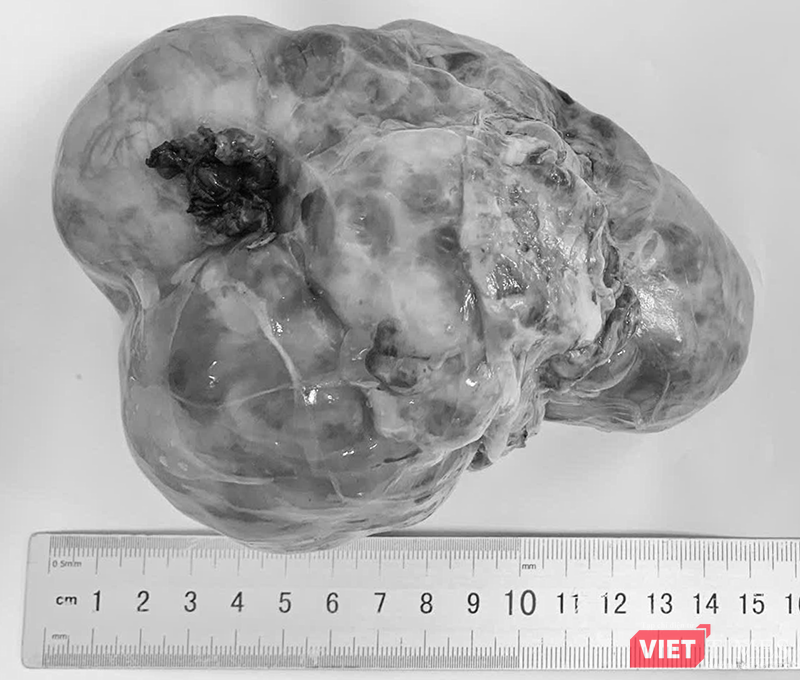

Khối u lấy từ ổ bụng của bệnh nhi được ê kíp bác sĩ Bệnh viện Phụ sản - Nhi Đà Nẵng thực hiện.

Theo BS.CKII Nguyễn Phi Phong, Trưởng khoa Ngoại, u nguyên bào thận là khối u ác tính ở thận thường gặp nhất ở trẻ, chiếm 5–7% ung thư nhi; độ tuổi hay gặp là 2–5 tuổi. U quái là khối u tế bào mầm, có thể lành hoặc ác tính và thường phát hiện muộn. Trong khi đó, u nguyên bào thần kinh chiếm khoảng 7–10% ung thư trẻ em và có tỷ lệ tử vong cao, xuất phát từ hệ thần kinh giao cảm.

Các bác sĩ cho biết u ổ bụng ở trẻ thường nằm sâu, triệu chứng nghèo nàn. Khi được phát hiện, đa số đã là khối u kích thước lớn, chèn ép cơ quan lân cận hoặc di căn, làm tăng độ phức tạp của điều trị.